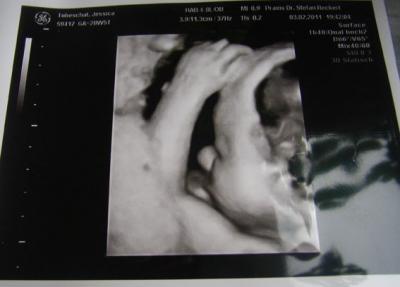

Er liegt jetzt auch endlich in SL und ich bekommen wieder Luft, ich hätte schon fast nen Sauerstoffzelt gebraucht *g* Allerdings mit dem Köpfchen nach hinten, er will sich einfach nich wirklich zeigen...3D Bildchen haben wir aber trotzdem bekommen, wenn auch nur von der Seite.

So hier die Bildchen